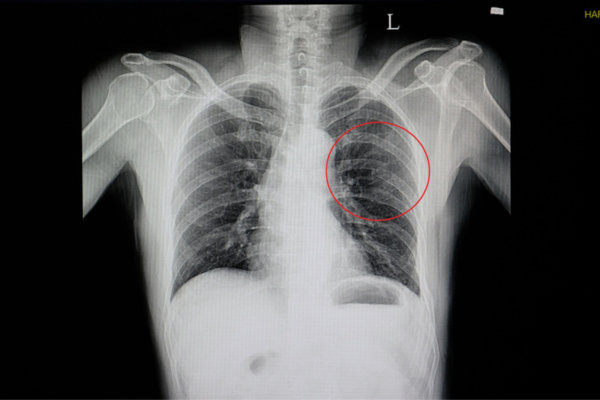

Η απλή ακτινογραφία θώρακος αποτελεί συνήθως την πρώτη απεικονιστική εξέταση, ωστόσο σε πολλές περιπτώσεις δεν επαρκεί για την πλήρη εκτίμηση των κακώσεων. Η αξονική τομογραφία θώρακος θεωρείται εξέταση αναφοράς, καθώς προσφέρει λεπτομερή απεικόνιση των καταγμάτων πλευρών ή στέρνου. Επίσης, επιτρέπει την εκτίμηση τυχόν μετατόπισης και τον έγκαιρο εντοπισμό συνοδών επιπλοκών. Η σωστή και έγκαιρη διάγνωση είναι καθοριστική για την επιλογή της κατάλληλης θεραπευτικής στρατηγικής και τη μείωση του κινδύνου επιπλοκών.

Παράδειγμα 3ο  Ασθενής με πρόσθια αριστερά κατάγματα πλευρών που δυστυχώς αντιμετωπίστηκαν συντηρητικά. Είχε πόνο για 18 μήνες και επιπρόσθετα κατέληξε με κήλη πνεύμονα στο κενό ανάμεσα στα πλευρά. Αντιμετωπίστηκε με χειρουργική επέμβαση και τοποθέτηση μοσχεύματος και λάμες με βίδες.

Το κίτρινο βέλος δείχνει το μεγάλο κενό ανάμεσα στις πλευρές